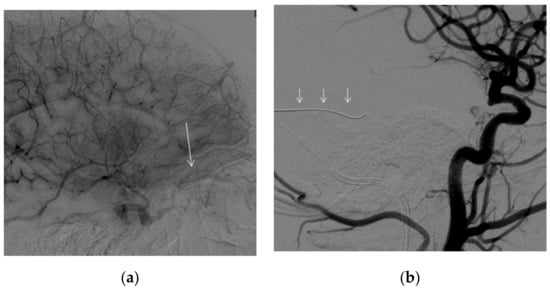

A transvenous approach was then attempted. The procedure was performed, under general anesthesia, through a venous and arterial femoral access. A full dose of 5.000 UI of intravenous unfractionated heparin (sodium heparin) was administered at the beginning of the procedure. On the venous side, we used a guiding catheter with the distal tip at the left jugular bulb. On the arterial side, we used a diagnostic catheter with the distal tip in the left maxillary artery for diagnostic purpose. From the venous side, we attempted with microcatheter and microguidewires to access the left inferior or left superior petrosal sinus to retrogradely access the diseased portion of the CS and occlude it with coils with a technique that has previously been described and is generally associated with high rates of success [8,9]. Nevertheless, despite several attempts, we could not negotiate the venous pouch (Figure 4a,b).

Figure 4. DSA. Embolization procedure. Left common carotid artery, lateral view. (a) Left inferior (arrow) and (b) left superior petrosal sinus (small arrows) catheterization. No access to the venous pouch of the fistula could be found.